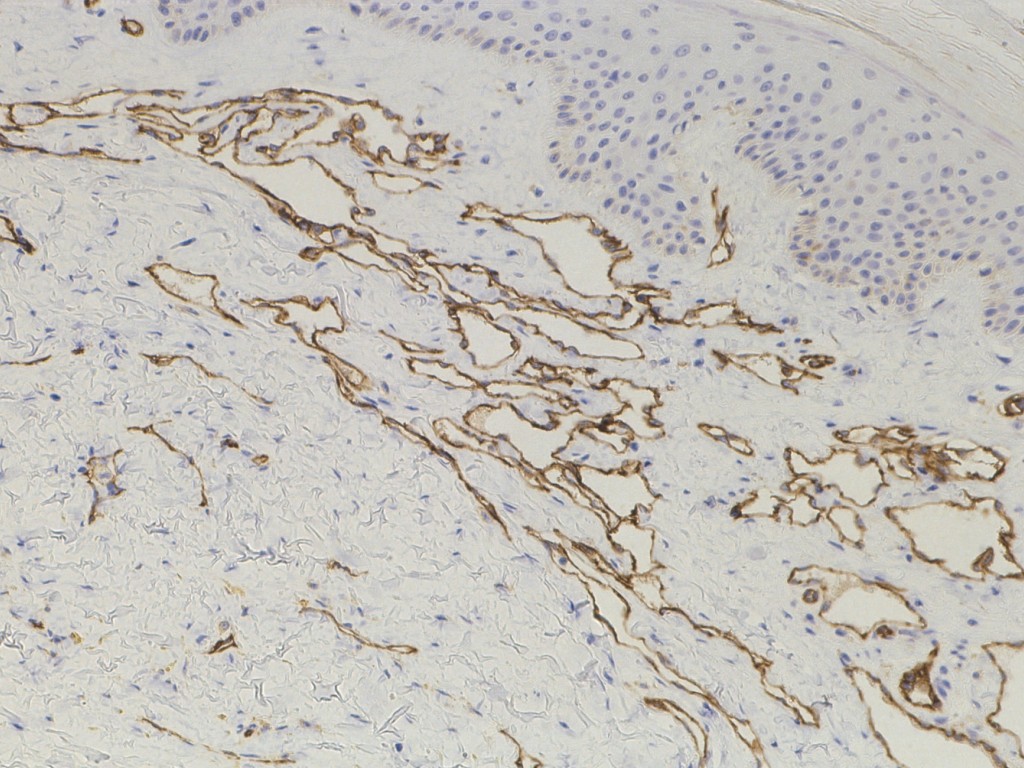

recente studies waarbij markers voor lymfvaten (D2-40 kleuring) zijn gebruikt

is gebleken dat het hobnail hemangioma eigenlijk geen hemangioom is maar een

lymfatische malformatie. Als nieuwe naam wordt

superficial hemosiderotic

lymphatic malformation voorgesteld.